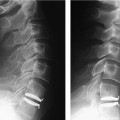

29 Migration of Polyethylene Core Device Migration, Dislocation, or Subluxation Fracture of the Vertebral Body Cerebrospinal Fluid Leakage and Root Injury Polyethylene Wear and Osteolysis Recent successful clinical results of lumbar disk arthroplasty have provoked widespread enthusiasm. The early- and intermediate-term clinical results of total disk replacement (TDR) were promising.1–15 Early results of prospective randomized studies comparing TDR with spinal arthrodesis have shown that TDR is doing as well or better than fusion.16–20 But the complications of TDR reported so far are neither rare nor minor in their potential severity. The incidence of complications even with experienced surgeons are not negligible and it is expected that the incidence will increase if TDR is widespread and done by less experienced surgeons.21 Furthermore, some of the reported complications are significantly dangerous and difficult to deal with.22 Therefore, it is worth appreciating all of the reported complications in this early period of enthusiasm to be aware of the real advantages and disadvantages of lumbar TDR and to avoid complications, if possible, when it is adopted in one’s own practice. This chapter discusses the complications of lumbar disk arthroplasty that are not related to surgical approach. Subsidence of the prosthesis is one of the common complications of TDR. It is generally regarded as a late complication of disk arthroplasty and Cinotti et al4 stated that subsidence occurred in patients who had an undersized prosthesis. In our series, however, subsidence occurred in the early postoperative period in relation to a fracture of the vertebral body (Fig. 29–1) or in patients with osteoporosis (Fig. 29–2). Marked subsidence and the resultant change in the configuration of the prosthesis could make the polyethylene core extrude. Because the extruded core may damage the great vessels that lie in front of the vertebral column, the prosthesis should be removed when the subsidence is identified in the immediate postoperative period or the configuration of the prosthesis is distorted significantly. However, in cases where the subsidence is not significant, reinforcement of the vertebral body with polymethyl methacrylate (PMMA) can prevent further sinking of the prosthesis (Fig. 29–2C). Technical error may be one cause of the subsidence. End plate preparation should be carefully done to make the plates of the prosthesis parallel because obliquity in the coronal plane may cause subsidence (Fig. 29–2A). The prosthesis should be positioned in the center of the coronal plane of the disk space to maintain the coronal balance of the spinal motion segment. Advanced segmental scoliosis preoperatively should be regarded as a relative contraindication of TDR because it is difficult to restore the scoliotic segment with an artificial disk. A patient with significant osteoporosis also should be excluded from TDR. In patients who have osteoporosis and refuse to accept fusion, augmentation of the vertebral body with PMMA may be a possible solution. There has been a successful report of concomitant augmentation of the vertebral body with PMMA in a patient with osteoporosis who underwent TDR,23 but long-term data are needed to prove its long-term efficacy. Delayed subsidence several years after the successful implantation of the prosthesis is another concern. When the vertebral body becomes osteoporotic as the patient ages, because of the discrepancy of the strength between bone and prosthesis, the prosthesis could subside. Although some investigators presumed that the porous-coated end plates (titanium and hydroxyapatite) would improve biological fixation of the metal plates to the vertebral bodies,24 it is uncertain that it could prevent late subsidence of the prosthesis. Figure 29–1 (A) Fifty-eight-year-old female. Lateral radiograph taken postoperative day 1 showed proper positioning of the implant. (B) On postoperative day 6, she felt severe back pain and radiography revealed subsidence of the implant with a transverse fracture of the L5 vertebral body. The prosthesis was removed and anterior lumbar interbody fusion was done. (Courtesy of Dr. Byung-Joon Kong.) There was a case of migration of the polyethylene core reported in the ProDisc series and it was attributed to technical fault.19 With the SB Charité (DePuy Spine, Raynham, MA) it occurred at the L5–S1 level where there was a large lumbosacral angle and hyperlordosis with a large distance between the two vertebral end plates anteriorly and a narrow posterior disk space. In such a case, David24 proposed to use the prosthesis with a more acute angle and place it more posteriorly. In our experience of 620 TDR cases, we have encountered one case of extrusion of the polyethylene core with resultant subluxation of the upper plate of the ProDisc (Synthes, Inc., West Chester, PA). In our opinion, the extrusion of the core is closely related to surgical technique. It is important to see that the core is securely positioned after the insertion. With the ProDisc, it is easy to see if the core is properly placed because the anterior margin of the core is at the same level of the device plates and it should not protrude over the edges of the plates of the prosthesis. With the SB Charité, it is better to confirm the position of the core with fluoroscopy because there is a metallic marker around the polyethylene core. Device migration or dislocations were reported in the study of previous models of the SB Charité (Charité I and Charité II)7,25 but with the SB Charité III, the incidence of migration or subluxation has decreased.4,5 With the ProDisc, though, there is no reported device migration or subluxation in the literature.8,11,12 We experienced a case of device subluxation in our ProDisc series. One reason that the ProDisc showed no incidence of device migration or subluxation may be that it has a high keel on the plates that gives more solid fixation in the immediate postoperative period than does the SB Charité. Fracture of the posterior corner of the vertebral body is a well-known complication of the SB Charité replacement (Fig. 29–3). The SB Charité has spikes on the anterior and posterior margin of the plates and these spikes can cause fracture of the posterior lips of the vertebral body during insertion of the prosthesis. It is better to prepare the posterior portion of the vertebral end plates adequately for smooth insertion of the prosthesis with a high-speed drill or a curette. It was also recommended that once the polyethylene core has been inserted, the prosthesis should not be hammered to be placed posteriorly.24 If the fracture of the posterior lip of the vertebral end plate is identified immediately after the surgery and the patient has symptoms of neural compression, the bony fragment should be removed by either an anterior or a posterior approach. We prefer the posterior approach because it can allow removal of the bony fragment compressing the thecal sac and root without the need to manipulate the prosthesis. Figure 29–2 (A) Sixty-two-year-old female. The immediate postoperative anteroposterior plain radiograph showed unparallel plates of L4–L5 prosthesis. (B)